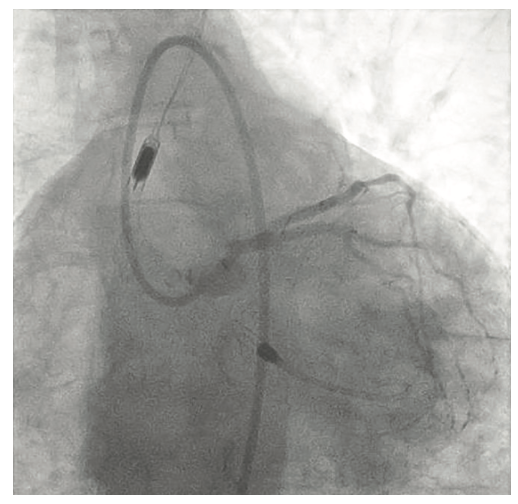

Following the Perclose placement, we upsized to a 14 Fr x 13 cm Cook Medical sheath (Figures 7-8), and through that, advanced a JR catheter into the ventricle and switched out for the Impella 2.5 device (Figure 9). A JR4 and eventually, an Amplatz right (AR) mod, was used from the right ulnar to engage the RCA, and an Extra Backup (EBU) 3.5, 7 Fr (Medtronic) was used from the groin. Dual angiography was performed (Figure 10). Once the activated clotting time (ACT) was >300 seconds, the ramus was wired with a Marvel wire (Boston Scientific). We attempted to cross the LAD CTO using a Corsair (Asahi Intecc) and a Pilot 200 (Abbott Vascular). The Pilot 200 crossed, but it appeared to be in the diagonal and could not be redirected down the LAD. A Gaia second (Asahi Intecc) was able to cross into the LAD (Figure 11), and at that point, was switched out via the Corsair for a workhorse wire, a Runthrough (Terumo). An 0.9 laser (Spectranetics) was used perform laser atherectomy for a minute and a half on the LAD (Figure 12), but we could not get the catheter across. However, this allowed us to advance a balloon across the lesion and we predilated with a 1.5 mm x 20 mm Mini Trek (Abbott Vascular) and then a 2.0 mm x 20 mm balloon. The same 2.0 mm x 20 mm balloon was used in the ramus. A 2.5 mm x 15 mm AngioSculpt (Philips) was used to predilate the LAD, but on its return, the AngioSculpt became stuck and would not come back. We got it partially into the guide and then the shaft broke. We had part of the catheter in the guide and part of it in the coronary (the left main). We initiated a series of procedures to remove the AngioSculpt, first attempting use of a GuideLiner (Vascular Solutions) to envelope the balloon, but this was unsuccessful (Figure 13). The GuideLiner kept pushing the device further out. We tried trapping it; that was also unsuccessful. We were able to get a Mini Trek balloon distal, thinking it could be inflated and pulled back; that did not work. We then put the 4 wires down, wrapped the wires around and pulled back, getting it partially in the guide, but we could not get it all the way in. We got a Mini Trek down, used the GuideLiner to put a 2.0 down, and attempted an anchor technique that did not work, but this time, when we pulled the Mini Trek 2.0 back, it dislodged the balloon. The AngioSculpt was able to come in the guide and was removed without losing wire position. We rewired the ramus, performed dilation of the LAD and ramus with a 2.5 mm noncompliant balloon, and performed intravascular ultrasound (IVUS). The LAD was about 2.75 mm2 distally and the ramus was 3.0 mm2, with the left main being approximately 3.75 mm2. A double kissing (DK) crush technique was used with a 2.75 mm x 38 mm Synergy stent (Boston Scientific) to the LAD and 3.0 mm x 24 mm Synergy to the ramus; then we used proximal optimization technique (POT) with a 3.75 mm NC balloon (Medtronic) and a final kiss with 3.0 mm x 20 mm NC balloons (Figures 14-17). IVUS was used to confirm that the stents were well apposed. The Impella device was weaned and removed, keeping the sheath in. From the groin sheath, a balloon was advanced into the left subclavian and we did a dry close. We inflated an 8.0 mm x 40 mm balloon at 3 atmospheres (nominal is 6 atmospheres) (Figure 18). Once the pressure tracing from the axillary sheath side arm dropped, we were able to remove the sheath and then completed the Perclose. There was some slight track ooze (Figure 19). Therefore, we performed two 5-minute inflations with the 8.0 mm x 40 mm balloon at 3 atmospheres (nominal is 6 atmospheres), and there was complete resolution of the track ooze. No extravasation was noted (Figures 20-21). The ulnar sheath was sutured in, we made sure there were no issues overnight, and the patient was discharged the following morning.